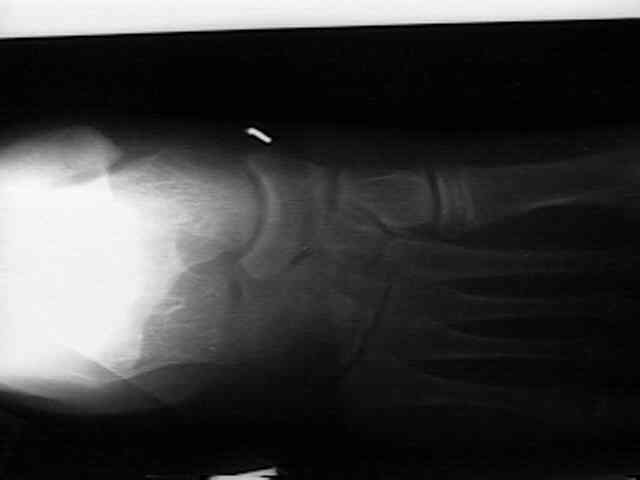

Radiographs

• radiographs may not be helpful if the accessory ossification is not ossified;

• the standard oblique of the foot (medial internal oblique view) will not show the accessory ossicle in profile;

• the lateral (external) oblique view is the radiograph of choice;

• although accessory navicular appears distinct from the navicular on x-rays, it is actually attached by fibrous tissue or cartilage;

Accessory Navicular 2 Accessory Navicular 3 Accessory Navicular 4